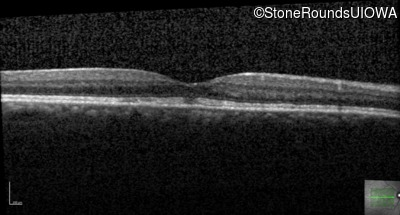

Optical Coherence Tomography - Right - 20/25 +2

Exemplar / OCT Stack

OCT Stack

Optical Coherence Tomography - Left - 20/50 -1